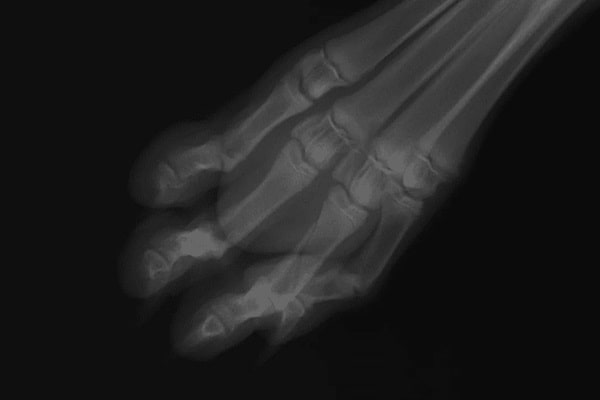

Пальця

Переломи пальців можливі, але вкрай рідко це входить у сферу інтересу хірурга. Такі пошкодження мало впливають на опороздатність. З цієї причини вони нечасто є причиною звернення в клініку.

Ще рідше можуть бути прийняті рішення щодо відновлювально-реконструктивної хірургії.

Зазвичай подібні травми підлягають самостійному загоєнню, на відміну від ушкоджень на сегмент вище. Переломи п’яти або плесна зазвичай вимагають хірургічної стабілізації. У цих випадках використовують комбінацію інтрамедулярної і зовнішньої стабілізації, оскільки інші методи фіксації в цій ділянці зазвичай малозастосовні.